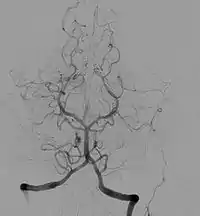

Angiographic image of normal cerebral anatomy. This illustration serves to show the reader the general circular shape of the roadmap of arteries that supply the brain. This is an x-ray image of the head after a radio-opaque dye was injected into the arterial system, the image is called an angiogram. For more detailed discussion of anatomy, see Circle of Willis.